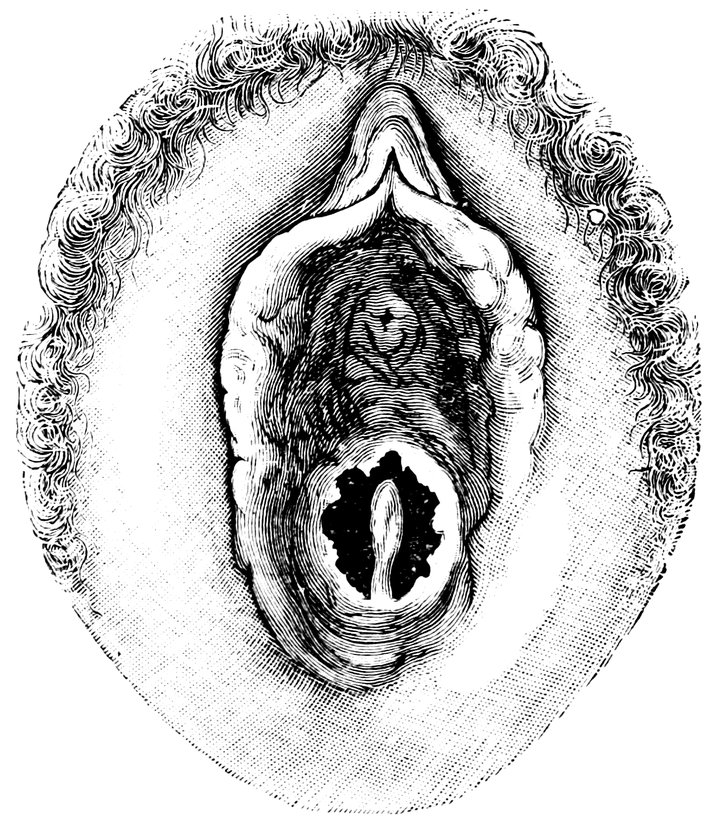

| 12. | Female external genital organs of a virgin | 54 |

| 13. | The external genital organs of a virgin | 55 |

| 18. | Annular Hymen | 64 |

| 19. | Annular Hymen | 64 |

| 20. | Semilunar Hymen | 65 |

| 21. | Annular Hymen with Congenital Symmetrical Indentations | 65 |

| 22. | Fimbriate Hymen | 65 |

| 23. | Deflorated Fimbriate Hymen | 65 |

| 24. | Septate Annular Hymen | 67 |

| 25. | Septate Semilunar Hymen | 67 |

| 26. | Extremely tough Annular Hymen with an obliquely disposed Septum | 67 |

| 27. | Septate Hymen with Apertures of unequal Size | 67 |

| 28. | Septate Hymen with Apertures of unequal Size | 68 |

| 29. | Hymen with rudimentary Septum | 68 |

| 30. | Hymen with posterior rudimentary Septum | 68 |

| 31. | Labiate Hymen with posterior rudimentary Septum | 68 |

| 32. | Hymen with anterior rudimentary Septum | 69 |

| 33. | Hymen with anterior rudimentary Septum projecting in a opiniform Manner | 69 |

| 34. | Hymen with anterior and posterior rudimentary Septa | 69 |

| 35. | Hymen with filiform Process projecting from the anterior Margin | 69 |

| 36. | Hymen in which there are two symmetrically disposed thinned Areas. The left of these is perforated | 69 |

| 37. | Very unusual form of Hymen | 70 |

| 38. | Semilunar Hymen with cicatrized Lacerations in its Border | 70 |

| 39. | Deflorated Semilunar Hymen with laterally disposed symmetrical Lacerations | 70 |

| 40. | Deflorated Annular Hymen with several cicatrized Lacerations | 70 |

| 41. | A. Septate Hymen in which defloration has been effected through one of the Apertures. U. Urethra. Cl. Clitoris. H. Cicatrized Margin. C. Septum. B. Lateral view of Septum | 70 |

| 42. | Deflorated Septate Hymen | 71 |

| x43. | Hymen with larger anterior and smaller posterior Apertures | 71 |

| 44. | Carunculæ Myrtiformes in a Primipara | 71 |

| 45. | Vaginal Inlet of a Multipara, without Carunculæ Myrtiformes. Slight Prolapse of Anterior and Posterior Vaginal Walls | 71 |